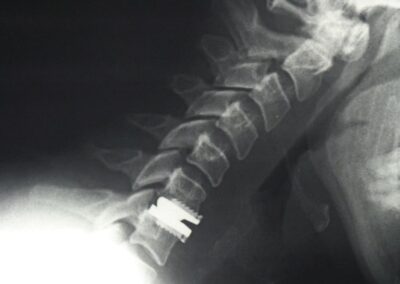

Cuando se trata de aliviar la presión sobre un nervio y el dolor de cuello, la cirugía usualmente incluye una extracción completa del disco o discectomía, seguido por el implante de un dispositivo espaciador o una prótesis total de disco. Esta cirugía se hace en la parte anterior del cuello (se le llama microdiscectomía y artrodesis o prótesis discal anterior). Afortunadamente, estos procedimientos muchas veces pueden realizarse usando técnicas de invasión mínima. La cirugía de invasión mínima no requiere incisiones grandes, sino que hace pequeños cortes y usa instrumentos y dispositivos minúsculos especializados durante la operación, como un microscopio y un endoscopio.